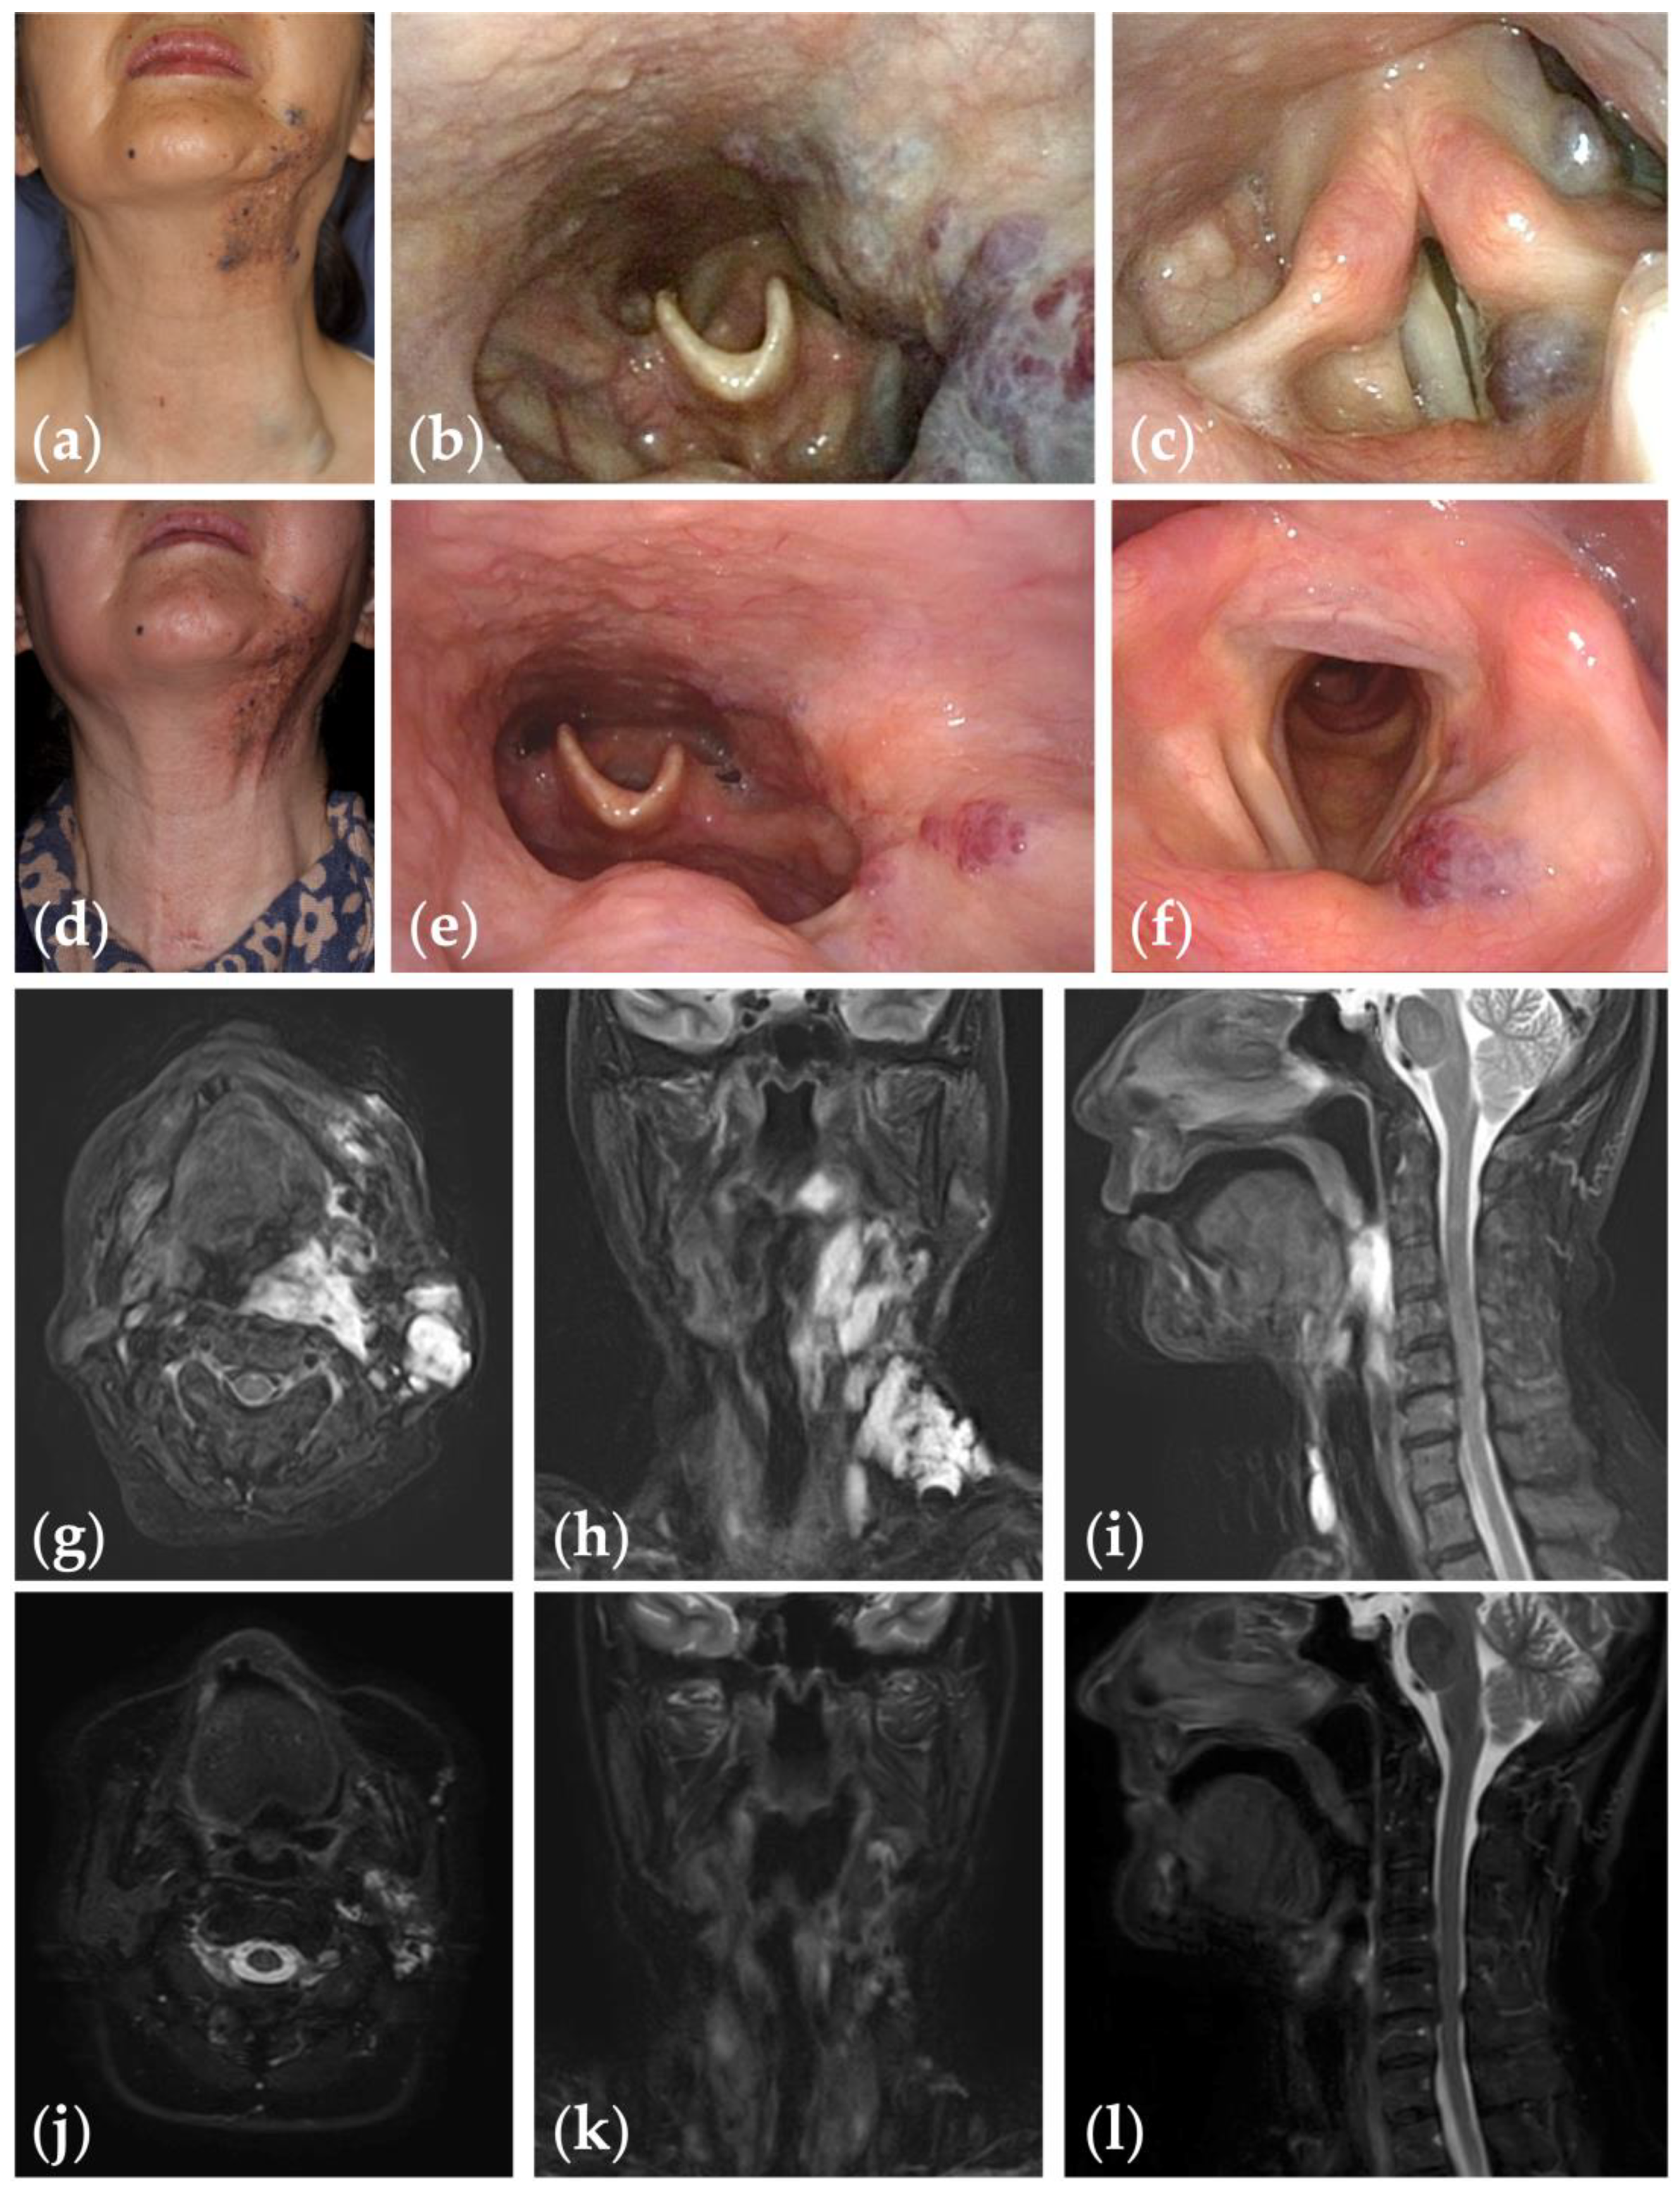

Patient 1 graded “excellent” for treatment outcomes after nine sessions of fluoroscopy- and endoscopy-guided transoral sclerotherapy: (a) initial clinical photograph, (b) endoscopic photographs of the pharynx; and (c) the glottis of a 67-year-old woman with oropharyngolaryngeal venous malformation; (d) clinical photograph; (e) endoscopic photographs of the pharynx; and (f) the glottis six months after the final sclerotherapy session at the age of 75 years; (g–i) fat-suppressed T2-weighted magnetic resonance images before treatment; (j–l) short tau inversion recovery T2-weighted magnetic resonance images six months after the final sclerotherapy session.